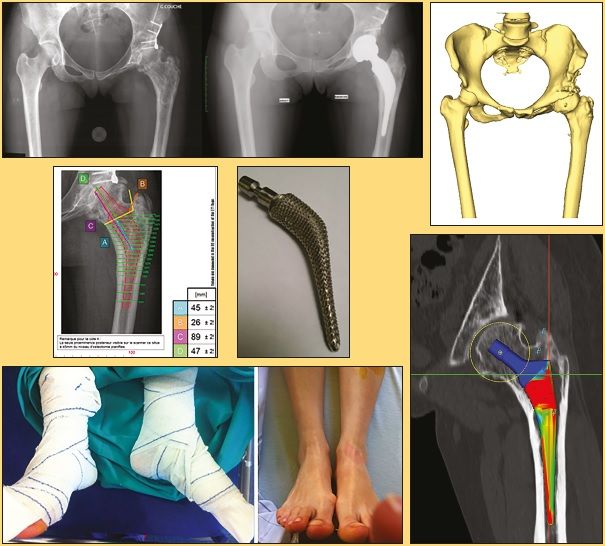

4/ Difficult cases

CT planning can be used to select made-to-measure arthroplasty indications. These indications derive from three main situations: small femurs (essentially dysplastic), femurs poorly adapted to standard implants (high offset with narrow intramedullary duct) and post-osteotomy femurs which often combine, to varying degrees, malunion, torsion disorder and unequal length. In my experience, 16 records out of 480 implants (3.4 %) required a made-to-measure arthroplasty. These records, which are difficult to analyse on standard x-rays, are easier to manager with the software (Fig 10 a and b).

Made-to-measure arthroplasty can be reduced to 0 %. It is almost always possible to place a standard or dysplastic implant, regardless of the situation encountered. This often requires compromise on the length, offset or anteversion. Conversely, made-to-measure arthroplasty has sometimes brought systematic prejudice. This is reported by the initial designers (1, 2, 3) using the made-to-measure implant by SYMBIOS in patients under the age of fifty. It is not currently a solution that can be used on a wide scale.

Where there is an indication for made-to-measure arthroplasty, the CT-scan is sent to the engineers, who will propose a made-to-measure implant. When you know how to use the software, you can discuss their proposal with the engineers, and approve or adjust it (often only by a few millimetres).

The 129° straight stem can be used in 85 % of situations. Tilted, high offset stems can be used in almost all of the other cases. 135° stems are now only used on rare occasions. In some cases, planning indicates that a made-to-measure implant would be more appropriate. This concerned 16 records out of 472 implants, representing 3.4 % of implants.

Step 1: The frontal and side on scout view can be used to perform length measurements outside and within the joint (Fig. 2).

Step 5: femur position: the software measures the posterior bicondylar line then defines a femur from the front and side on (Fig. 5). The greater trochanter, the digital fossa and the lesser trochanter landmarks can thus be specified. All of these measures are used to define the femoral torsion and offset.

Step 6: femoral stem planning: we can position a stem, choose the size, evaluate bone stress, measure bone resection (that we can compare during surgery using the callipers) and choose the ball (Fig. 6 and 7). The software calculates lengthening and offset depending on the implants selected.